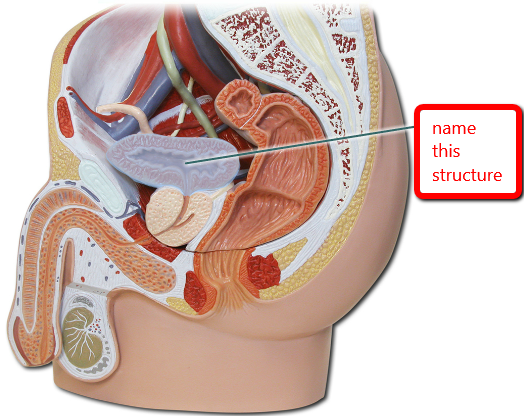

Uterus

Myometrium

Endometrium

Perimetrium

Broad ligament

Round ligament (of uterus)

Overian ligament

Uterine (=fallopian) tube

Ovary

Urinary Bladder (female)

Vagina